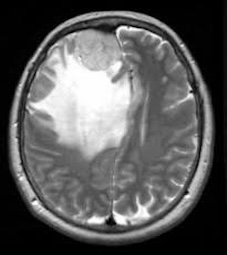

Brain Tumor MRI dataset:

The Brain Tumor MRI Images dataset is a publicly available dataset on Kaggle555https://www.kaggle.com/datasets/sartajbhuvaji/brain-tumor-classification-mri/data. It contains MRI images of human brains divided into four categories: No Tumor, Pituitary Tumor, Benign Tumor, and Malignant Tumor. For our study, we selected three categories: No Tumor (NT), Benign Tumor (BT), and Malignant Tumor (MT). From each category, we chose three MRI images representing different parts of the brain that best illustrate the characteristics of each class. The categories included in this study are described as follows:

The No Tumor (NT) category contains MRI images of healthy brains with no abnormal growths or masses. In these images, the brain tissue appears normal, and there are no signs of tumors or unusual structures. These images serve as a baseline, allowing for effective comparison and detection of abnormalities in other MRI scans.

Refer to caption

(a) NT1

(b) NT2

(c) NT3

(d) BT1

(e) BT2

(f) BT3

(g) MT1

(h) MT2

(i) MT3

Figure 5. Axial and Coronal MRI Images of Brains Representing Different Tumor Categories

The Benign Tumor (BT) category includes MRI images showing non-cancerous tumors in the brain. Benign tumors grow slowly and do not spread to other parts of the brain or body. While generally less dangerous than malignant tumors, they can still cause symptoms if they press on surrounding brain tissue. Accurate identification of benign tumors is important for planning appropriate treatment, which may involve monitoring, minor surgery, or other non-aggressive interventions.

The Malignant Tumor (MT) category consists of MRI images showing cancerous tumors. These tumors are aggressive, can grow rapidly, and may spread to other parts of the brain or body. Malignant tumors require immediate and intensive treatment, such as surgery, chemotherapy, or radiotherapy. Differentiating malignant tumors from benign tumors is crucial, as it directly impacts the treatment strategy and can significantly affect patient outcomes.

Differentiating these categories is essential for early detection, accurate diagnosis, and effective treatment planning. By distinguishing between healthy brains, benign tumors, and malignant tumors, medical professionals can identify abnormalities more reliably, reduce misdiagnoses, and streamline medical care. In this study, we apply our divergence measure to differentiate between the selected MRI images, as illustrated in Figure 5. In Figure 5, the first row shows MRI images from NT patients, the second row shows images from BT patients, and the third row shows images from MT patients.

Using the divergence measure, we calculated estimates for each pair of MRI images and compared the three categories. For calculation, each grayscale image is represented by its pixel intensity values (scaled to [0,1]). These values are flattened into a one dimensional vector and used as the sample data for subsequent analysis. For any two images, denoted data1 and data2, we then computed an empirical based divergence estimate. The resulting values are presented in Tables 4, 5, and 6. A higher value of the divergence estimate indicates a greater likelihood of a tumor. These results demonstrate that the divergence measure can serve as an effective tool for detecting tumors in medical image data.

While our study demonstrates the effectiveness of the divergence measure in differentiating brain MRI images across tumor categories, the results could be further strengthened with longitudinal data, where MRI scans of the same individuals are available at different stages of tumor progression, captured with consistent size and image quality. The current dataset, being cross-sectional, limits the ability to draw more definitive conclusions regarding tumor evolution. Incorporating longitudinal data in future studies would provide deeper insights and allow for more robust validation of the divergence measure in tracking disease progression.